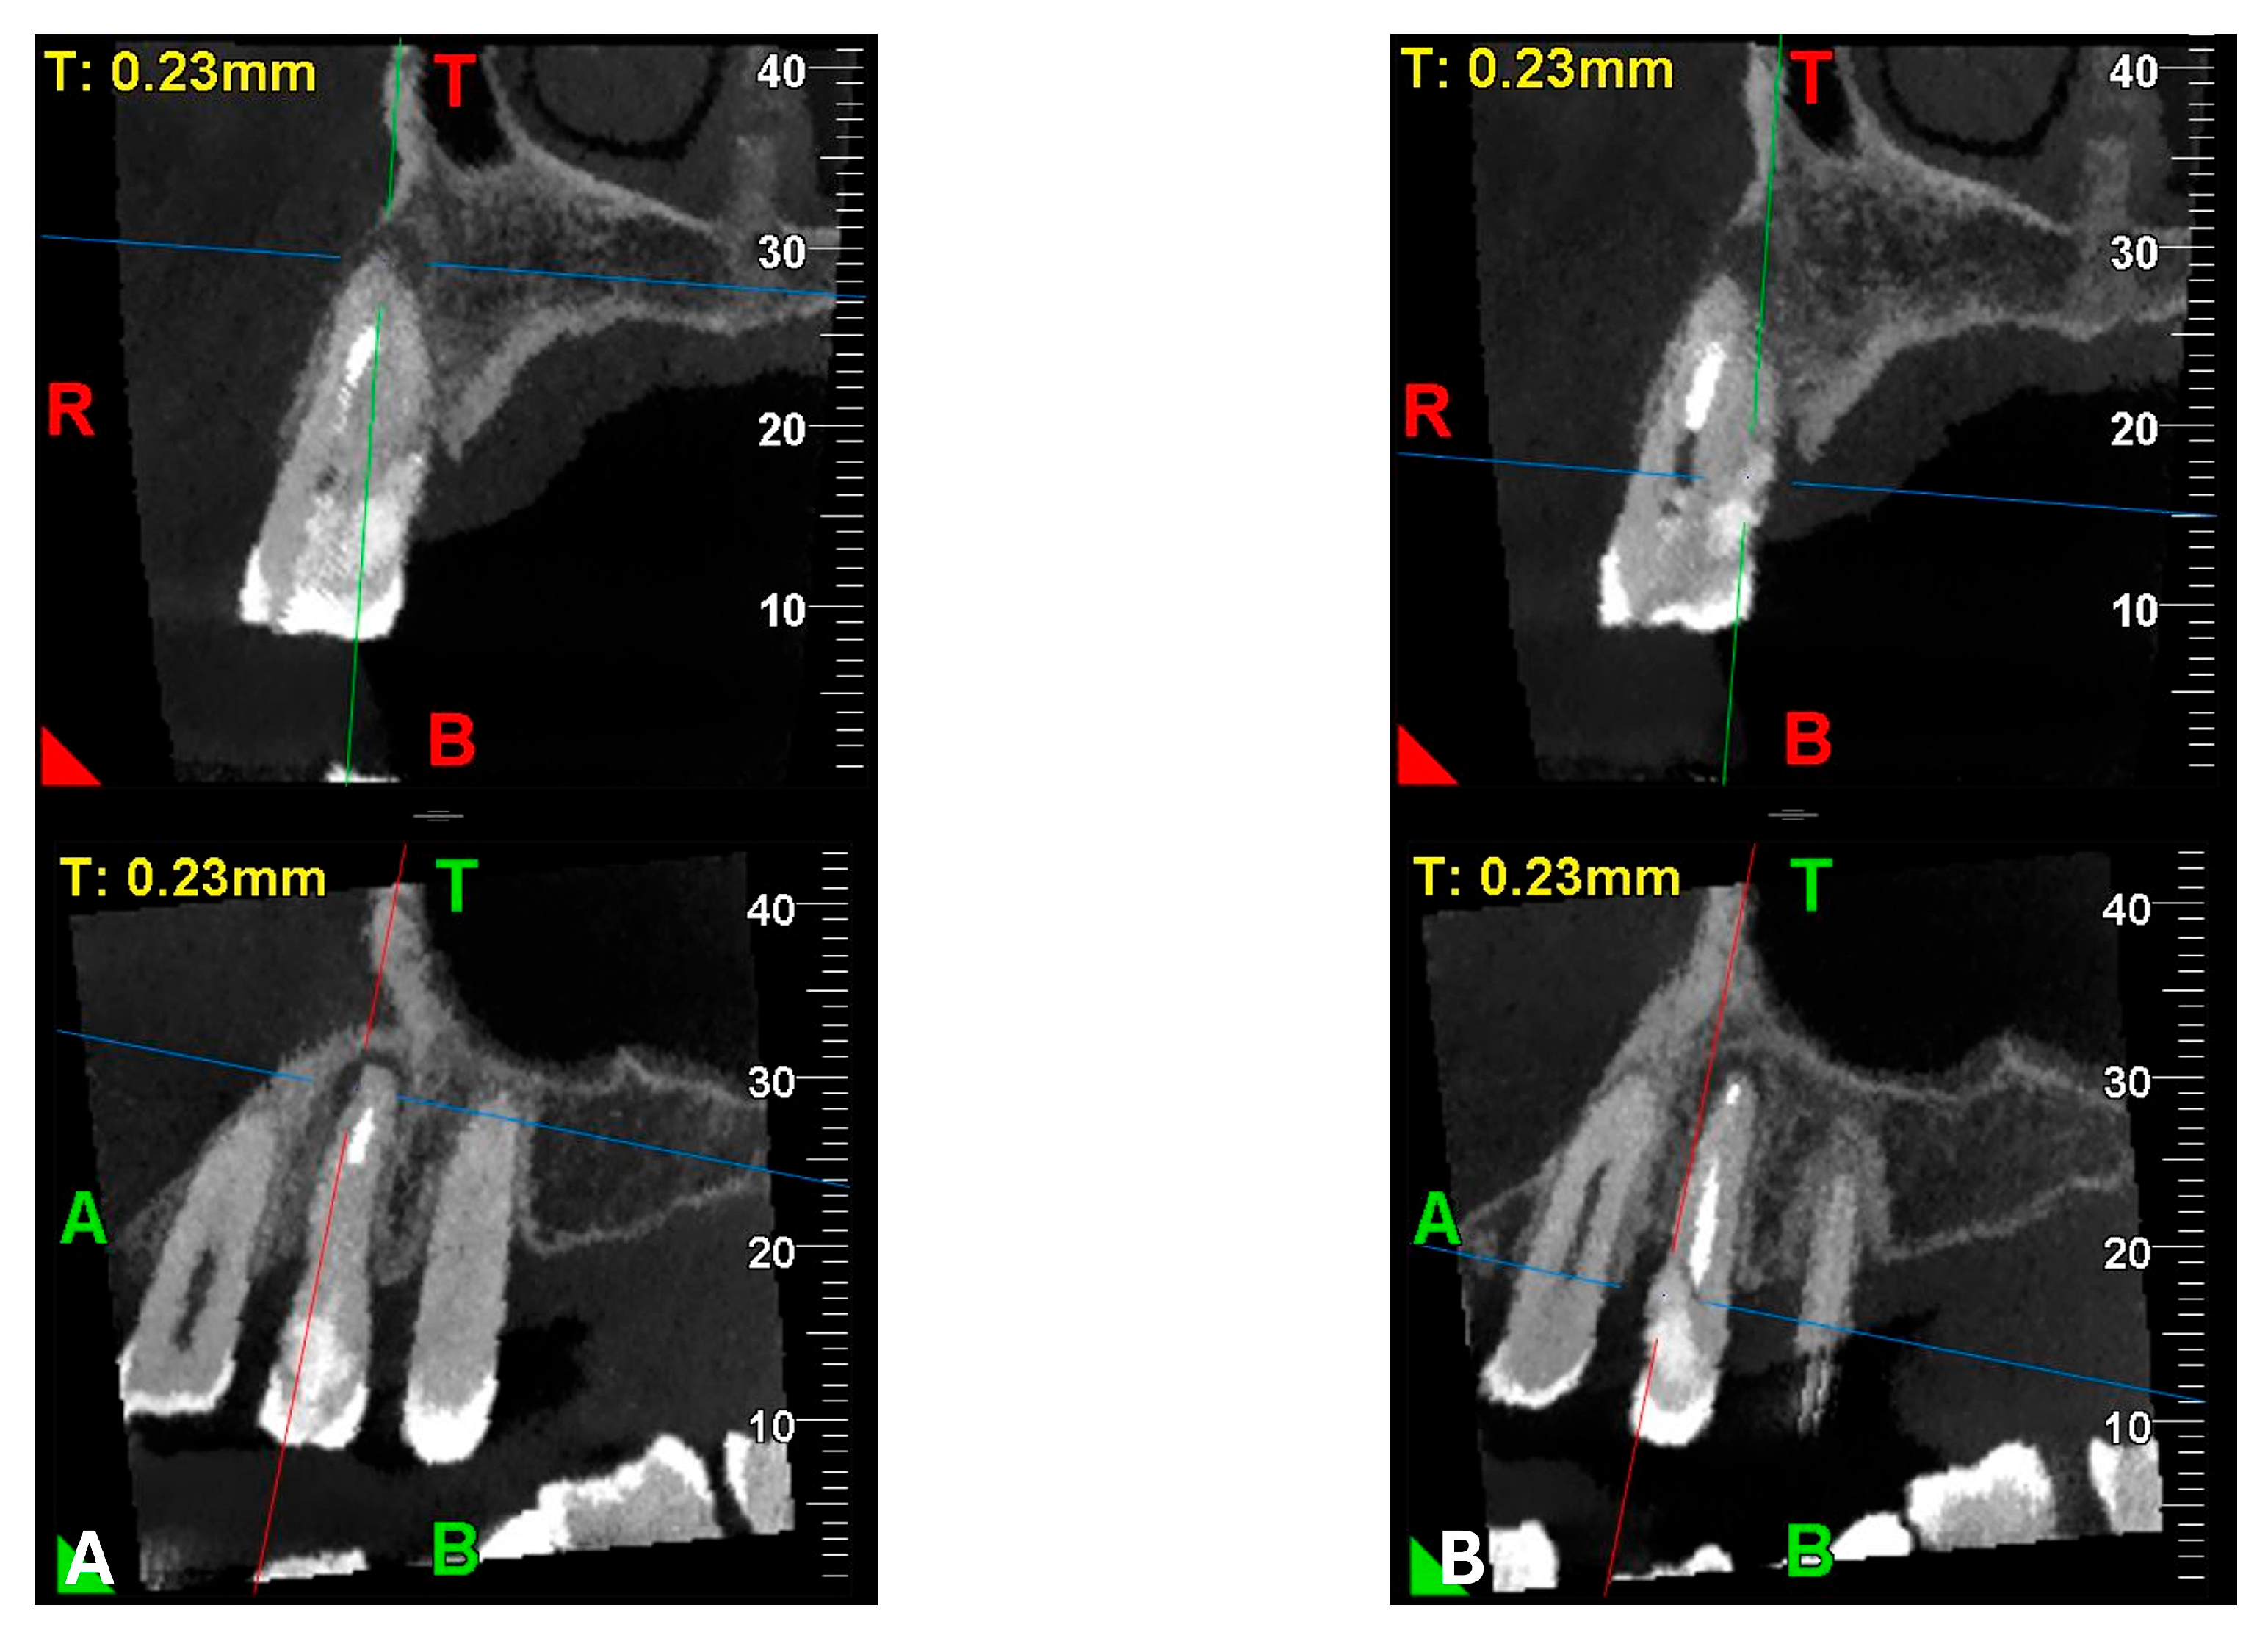

Figure 3.

Cross-section and Pano-rex CBCT images of tooth 1.4 and its ECR and EPL. (A,B) Sequential sagittal scrolling allows the evaluation of the lesion in the bucco-lingual direction and its continuity along the root axis; (C,D) Segmentation of Figure 3B using the advanced software functions iRYS® (MyRay, Imola, Italy); (E) Interface of the aforementioned software to obtain segmentation on Pano-rex image. (F) Pano-rex image of tooth 1.4 and its EPL. (G,H) Segmentation of Figure 3F using the advanced software functions. The colored lines crossing the images represent the orthogonal planes (axial, coronal, and sagittal) in the multiplanar reconstruction. Their correct use and orientation allow for an accurate identification of the extent of the lesions in all spatial planes and a detailed analysis of the endodontic anatomy. The green letters are the coordinates of the image: A: anterior, B: bottom, T: Top.

A CBCT examination (X9 Pro®, MyRay, Imola, Italy), performed with dedicated field of view (FOV) (6 × 6) and exposure parameters, was essential for accurate diagnosis and treatment planning. This device optionally features a specific Booster function for users with advanced expertise, which allows for further customization of exposure parameters to optimize the examination more effectively. Optimal management of the FOV, properly centered and limited to the anatomical area of interest, in this specific case slightly extended (6 × 6) to clearly rule out a possible involvement of the maxillary sinus in agreement with the attending otorhinolaryngologist, enabled the acquisition of broader and more detailed clinical and diagnostic information, which is essential in endodontics. Moreover, it allowed for a significant reduction in radiation dose while optimizing spatial resolution [22]. The imaging clarified the extent of the resorption and defined its perimeter, demonstrating an endodontic-periodontal communication, classified as 3Bp according to Patel’s classification [21] (Figure 2, Figure 3, Figure 4 and Figure 5).